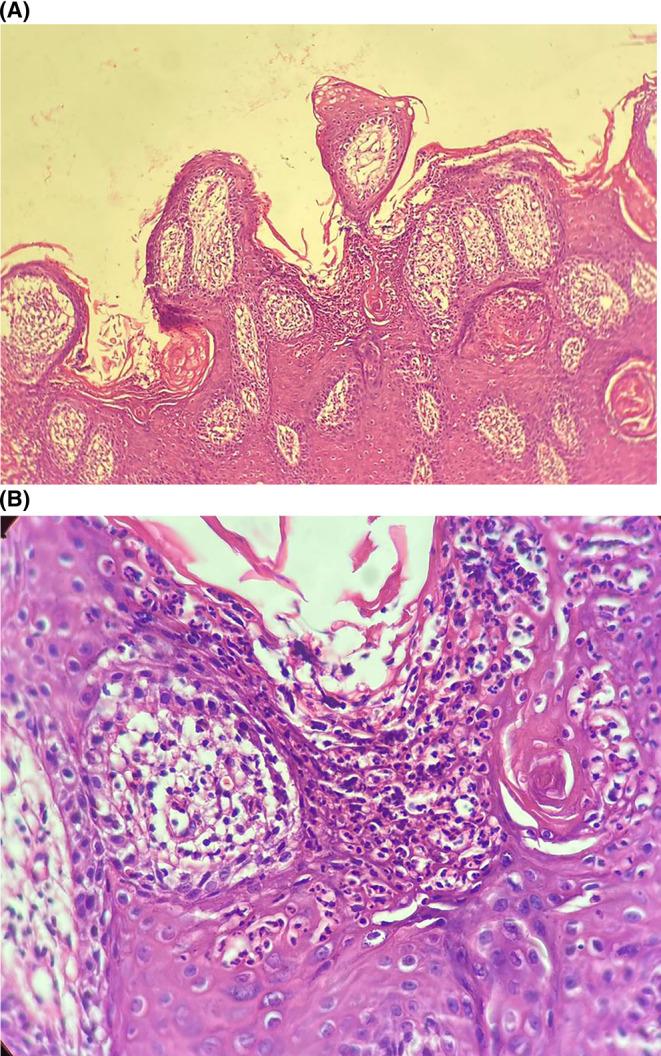

Epidermal nevus superimposed by psoriatic plaque in a girl with proteous syndrome.

Proteus syndrome (PS) is a rare syndrome characterized by asymmetric limb overgrowth, vascular malformation, and hamartomas. In this study we report a case of PS in a 13-year-old girl with chief complaint of a new cutaneous lesion that was diagnosed and treated as leishmaniasis.